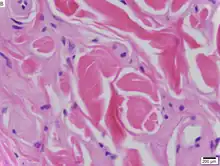

The dermatological symptoms are caused by a buildup of a hyaline material in the dermis and the thickening of the basement membranes in the skin.[9] The nature of this material is unknown, but researchers have suggested that it may be a glycoprotein, a glycolipid, an acid mucopolysaccharide, altered collagen or elastic tissue.[6]

Urbach–Wiethe disease is typically diagnosed by its clinical dermatological manifestations, particularly the beaded papules on the eyelids. Doctors can also test the hyaline material with a periodic acid-Schiff (PAS) staining, as the material colors strongly for this stain.[6]

Immunohistochemical skin labeling for antibodies for the ECM1 protein as labeling has been shown to be reduced in the skin of those affected by Urbach–Wiethe disease.[13] Staining with anti-type IV collagen antibodies or anti-type VII collagen antibodies reveals bright, thick bands at the dermoepidermal junction.[9]